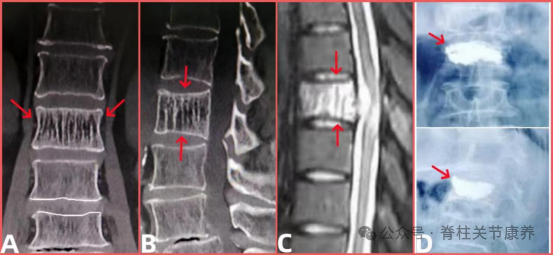

1. 确诊:核磁是“金标准”

既然是核磁检查发现的,那它就是确诊的主要手段。核磁能清晰看到血管瘤的大小、位置、区分它和其他骨头问题(比如骨质疏松、骨质增生),一般不用再做其他复杂检查。